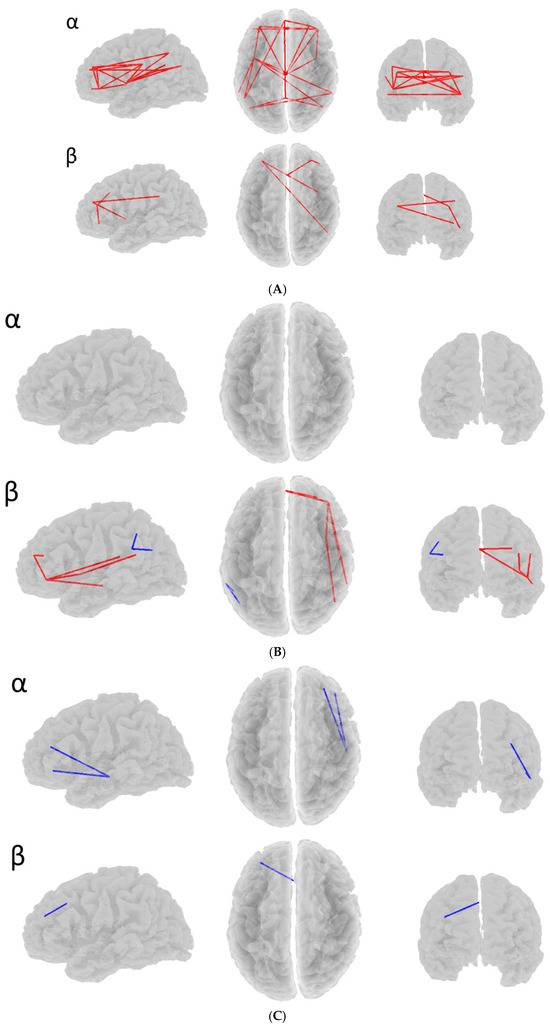

| SDS Subtype | Dm 1 | Dm | Da | Da | Dc | Dc | Ds | Ds |

|---|---|---|---|---|---|---|---|---|

| Band | α | β | α | β | α | β | α | β |

| D > ND 2 | 0 | 0 | 0 | 2 | 2 | 1 | 2 | 0 |

| D < ND | 20 | 4 | 14 | 6 | 0 | 0 | 6 | 2 |

| Best p from eLORETA | 0.048 | 0.186 | 0.369 | 0.130 | 0.245 | 0.228 | 0.059 | 0.222 |